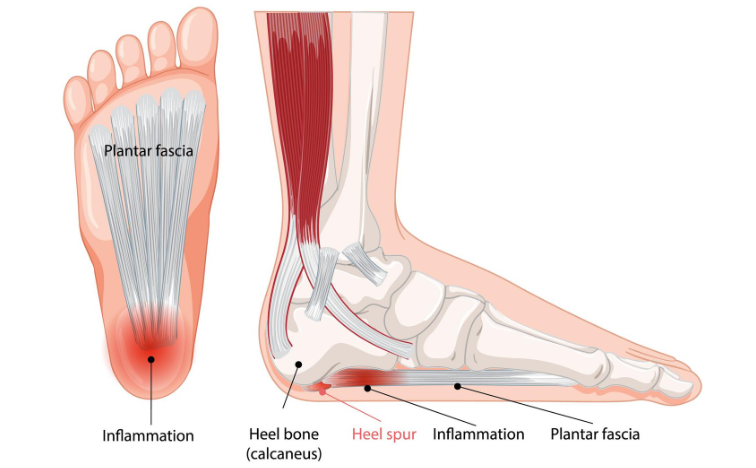

Plantar fasciitis is a condition affecting the plantar fascia, a thick, web-like ligament that runs from your heel to the front of your foot. This tissue band absorbs shock and supports your foot’s arch. The plantar fascia can develop small tears when subjected to excessive tension and stress.

Repeated stretching and tearing can inflame the fascia, leading to the hallmark symptoms of plantar fasciitis. This condition is an overuse injury that is particularly common in: